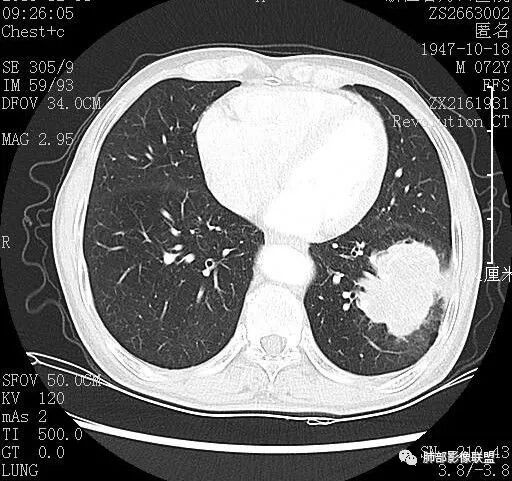

脐凹?边缘膨隆

边缘膨隆,血管走形其中似远端破坏

但是远端部分很散,边界清楚,应该是周围伴有炎症

看一下病灶主体,支气管堵塞

1.支气管截断

2.边缘模糊磨玻璃。

3.形态主体有明显膨隆,边缘有很多散发的病变边缘平直

4.远端有树丫,提示炎症一定存在的

5.淋巴结稍大

6增强后有很多坏死,与实性成分分界不清

7.脐凹?

总结

结合年龄主要考虑的有:肺癌,与之非常相似的结核和隐球菌。。。隐球菌应该强化比较均匀不符合。主要是肺癌和结核鉴别,年轻,空洞,树丫,结核是需要考虑。但是边缘膨隆,强化不均匀,支气管堵塞,可疑脐凹,这些都比较支持恶性,建议支气管镜吧,比较少见的坏死性肉芽肿还有放线菌这种慢性炎症。